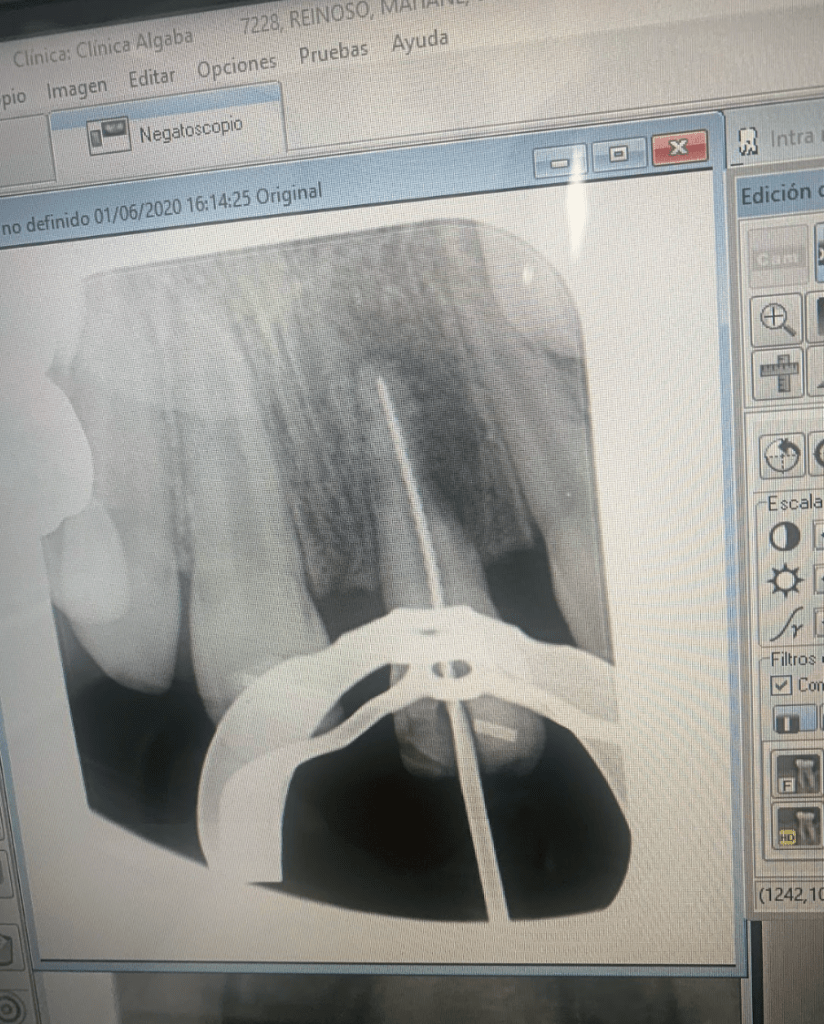

Avulsión incisivo central